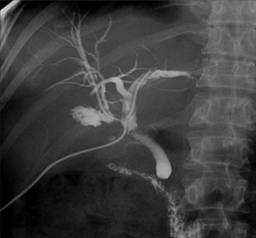

Las lesiones iatrogénicas del conducto biliar (IBDI) siguen siendo un problema significativo en la cirugía gastrointestinal debido a la complejidad del sistema biliar y los riesgos asociados con su manejo durante las intervenciones quirúrgicas. Estas lesiones ocurren cuando el conducto biliar, que es el tubo que transporta la bilis desde el hígado hasta el intestino delgado, se daña inadvertidamente durante una cirugía.

La causa más común de estas lesiones es la colecistectomía laparoscópica, un procedimiento quirúrgico en el que se extrae la vesícula biliar a través de pequeñas incisiones en el abdomen, utilizando una cámara y herramientas especializadas. Este tipo de cirugía se ha convertido en uno de los procedimientos más frecuentes a nivel mundial debido a sus beneficios, como menor tiempo de recuperación y menos dolor postoperatorio en comparación con la cirugía abierta tradicional.

Sin embargo, a pesar de su popularidad y sus ventajas, la colecistectomía laparoscópica implica un riesgo considerable de daño al conducto biliar. Esto se debe a la anatomía compleja de la zona, que puede ser difícil de visualizar con precisión a través de las pequeñas incisiones. Además, la posibilidad de una identificación incorrecta de los conductos biliares durante la cirugía puede llevar a lesiones inadvertidas. La visualización limitada y la necesidad de manipular estructuras delicadas en un espacio reducido aumentan el riesgo de dañar el conducto biliar.

La elección del tratamiento adecuado para las IBDI es crucial, ya que puede evitar estas complicaciones graves y mejorar la calidad de vida de los pacientes. Por lo tanto, la cuestión sobre el tipo de tratamiento para los pacientes con IBDI sigue siendo un tema de debate. Inicialmente, se recomienda el tratamiento endoscópico en pacientes con IBDI. Cuando las técnicas endoscópicas no son efectivas, se realizan diferentes reconstrucciones quirúrgicas. El objetivo del tratamiento quirúrgico es la reconstrucción para permitir un buen flujo biliar hacia el tracto alimentario. Para lograr este objetivo, se utilizan muchas técnicas. Existen opiniones contradictorias sobre las diferentes reconstrucciones quirúrgicas en la literatura.

El tratamiento inicial recomendado para las IBDI suele ser endoscópico. Las técnicas endoscópicas son menos invasivas y se realizan a través de un endoscopio, un tubo delgado con una cámara y herramientas pequeñas, lo que permite a los médicos visualizar y tratar el área afectada sin necesidad de una cirugía mayor. Estos métodos pueden ser efectivos para resolver el problema en algunos casos, especialmente cuando la lesión es relativamente menor o localizada. La ventaja de los tratamientos endoscópicos es que suelen implicar menos riesgos y una recuperación más rápida en comparación con las intervenciones quirúrgicas más extensas.

Sin embargo, cuando las técnicas endoscópicas no logran el resultado deseado, se deben considerar opciones quirúrgicas más complejas. La cirugía en estos casos busca reconstruir el conducto biliar para restaurar el flujo normal de bilis hacia el tracto digestivo. Esta reconstrucción es esencial para asegurar que la bilis pueda fluir adecuadamente, evitando así la acumulación y los problemas asociados que pueden surgir de un flujo biliar bloqueado o alterado.